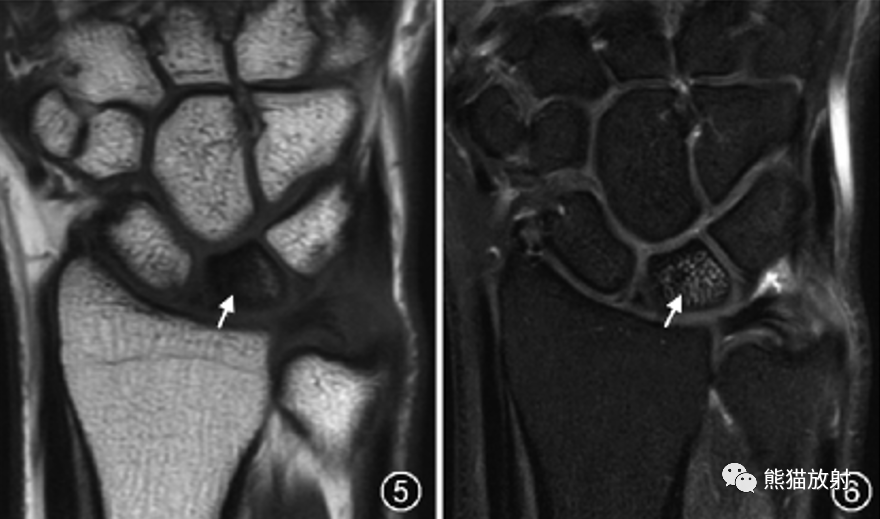

尺骨撞击综合征常见的鉴别诊断:Kienböck′s病。Kienböck′s病时,月骨内异常信号更加弥漫或主要累及月骨桡侧(图5,6),而尺骨撞击综合征时,月骨内异常信号累及月骨尺侧面。此外,Kienböck′s病时,尺骨头和三角骨通常不受累。

图5,6 Kienböck′s病。女,32岁,左腕关节疼痛。腕关节冠状位T1WI(图5)和质子密度加权脂肪抑制序列图像(图6)示尺骨负向变异,月骨内弥漫性不均匀T1WI低信号、脂肪抑制序列呈不均匀高信号(↑),与尺骨撞击综合征主要累及月骨近端尺侧面不同。